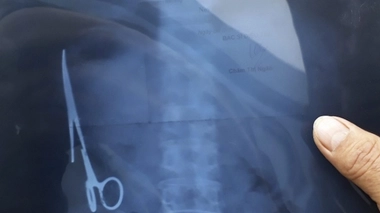

Un instrument chirurgical retrouvé dans le ventre d'un Vietnamien 18 ans après son opération

photographie de la radio de l'estomac © MAXPPP/STRINGER/EPA .jpg